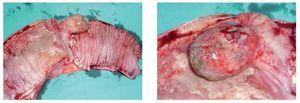

Caso 2: Paciente con lipoma obstructivo de íleon terminal. Hombre de 60 años, que ingresó por historia de un año de evolución con cuadros de obstrucciones intestinales parciales de repetición. Negó pérdida de peso o episodios de sangrado. La tomografía computada demostró engrosamiento del íleon terminal y del ciego, con adenopatías pericecales. La colonoscopía no evidenció lesiones hasta el ciego. Se le realizó hemicolectomía derecha laparoscópica por un solo puerto. El análisis histopatológico confirmó la presencia de un lipoma de íleon terminal (Figuras 4 y 5). El paciente tuvo una buena evolución post-operatoria y egreso al tercer día, sin complicaciones.

¿ Figura 4 y 5. Pieza quirúrgica del lipoma obstructivo del íleon terminal.